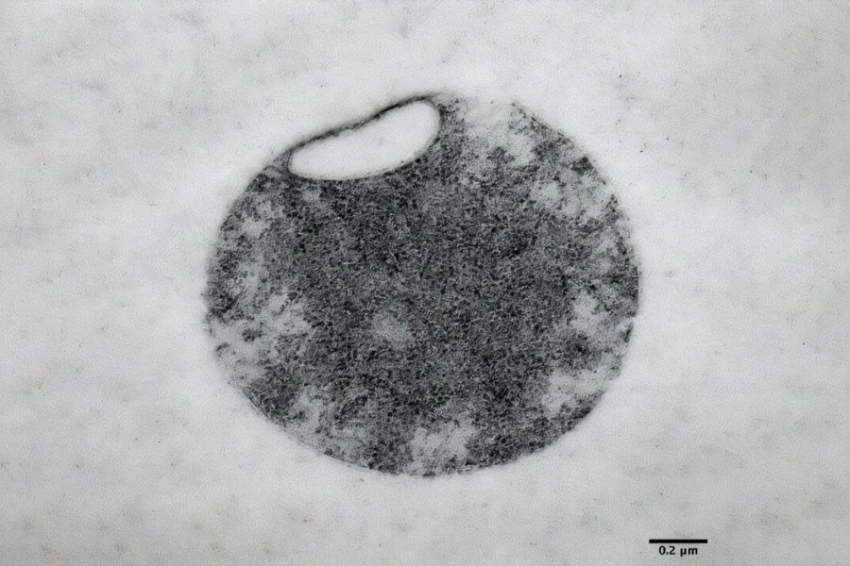

В процессе исследования ученые обнаружили, что с возрастом у червей значительно сокращается объем шероховатого эндоплазматического ретикулума, который играет ключевую роль в синтезе и сворачивании белков. В то же время изменения в гладком ретикулуме, связанном с обменом липидов, оказались менее выраженными.

Механизм ЭР-фагии

Клетки нематод перестраивают свою систему с помощью механизма, называемого ЭР-фагией. Это разновидность аутофагии, при которой клетка расщепляет и перерабатывает поврежденные или ненужные элементы. В процессе ЭР-фагии избирательно удаляются отдельные участки эндоплазматического ретикулума, что позволяет клеткам адаптироваться к изменениям.